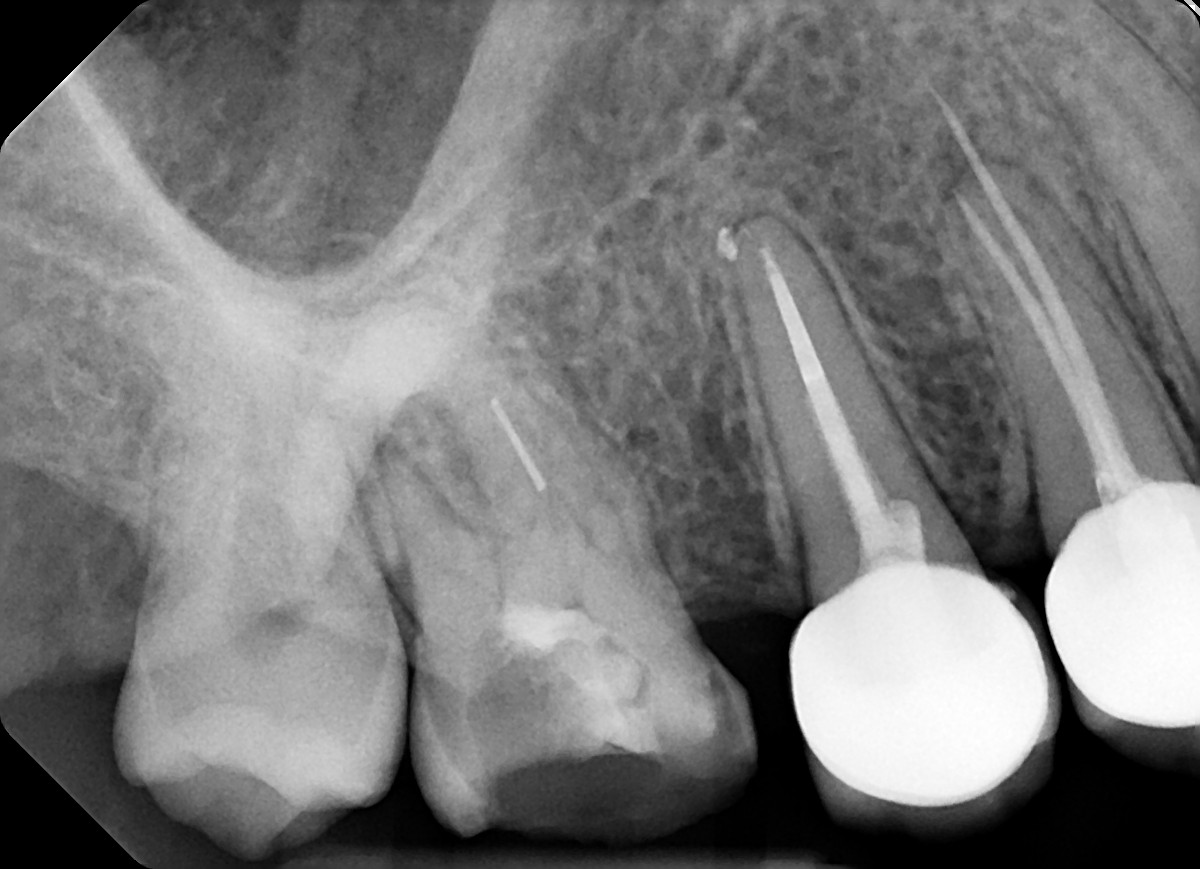

1. Evaluate the root canal treatment of tooth # 2.5?

2. What option cannot be selected for root canal treatment of tooth # 2.6?